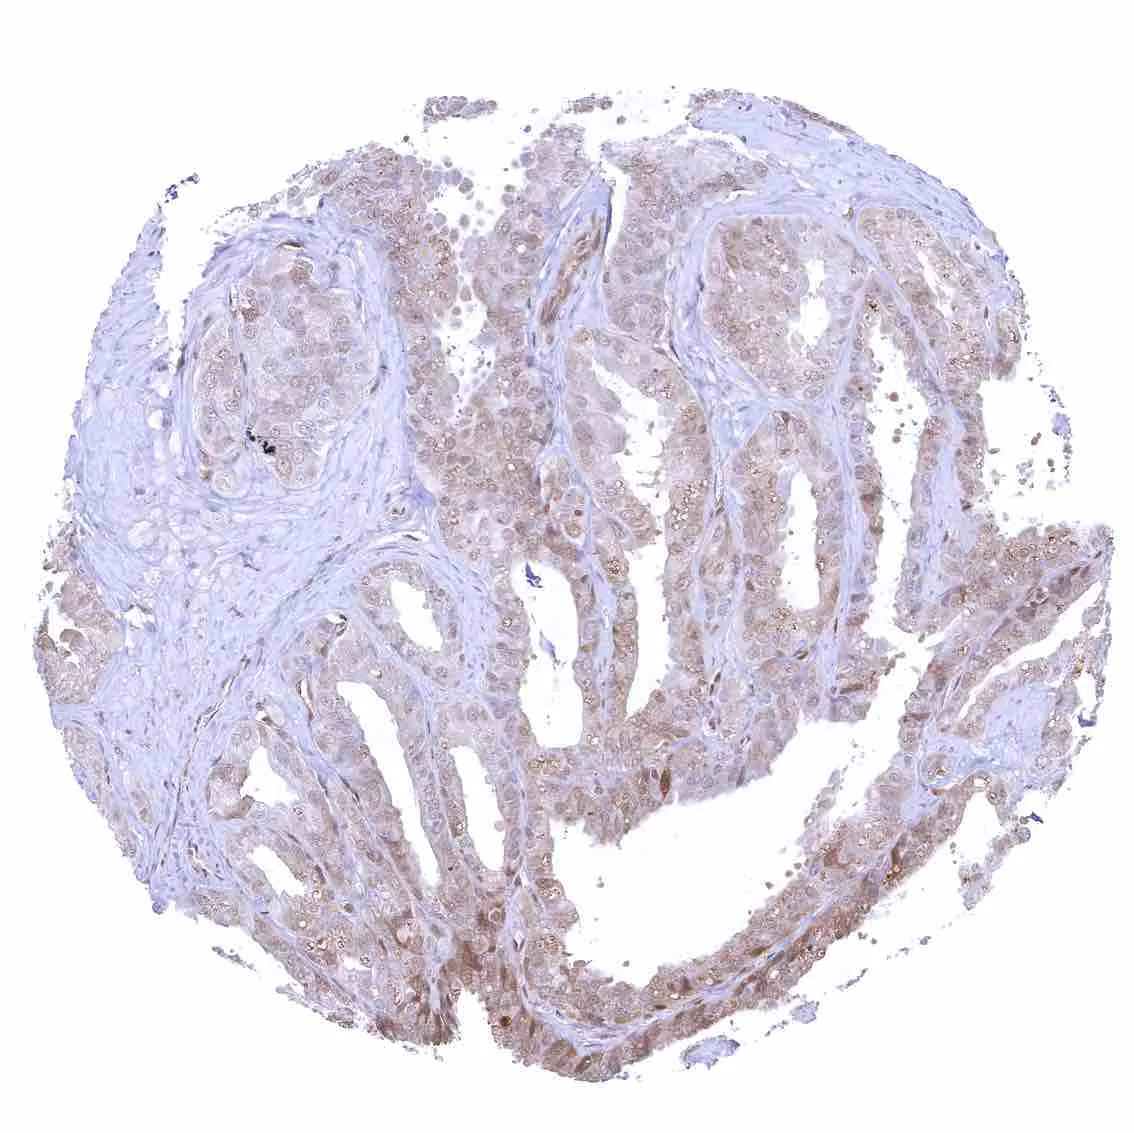

Pancreas – p27 staining is more common in islet cells than in acinar cells.